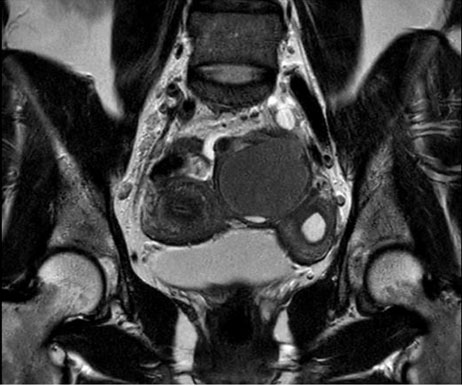

The MRI scan showed a unicornuate uterus with dilatation of the hypotrophic, non-communicating left horn with blood pooling (Figure 1A and Figure 1B). It also showed a right tubo-ovarian complex with a likely endometrioma with recent blood. On the left side a large tubo-ovarian complex with hematosalpinx with large endometrioma (5.5 cm) and encapsulated serosanguinous fluid adjacent to the ovary could be seen. The sacro-uterine ligaments were bilaterally thickened with underlying cysts right paramedian, extending to the adjacent wall of the distal sigmoid with no deep bowel infiltration (Figure 2).

Figure 1: (A and B) T2 and T1 MRI image of the congenital anomaly with a unicornuate uterus (right cavity normal) and a hypoplastic, non-communicating left horn; dilation of the left horn containing blood. Discrete hemorrhagic endometriosis foci adjacent to the serosa on the left.

Figure 2: T2 MRI image of the two horns of the uterus with the left ovarium endometrioma in between.